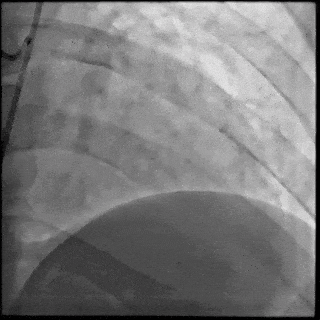

【DSA图1.左冠治疗前造影】

5月28日8:00,葛均波院士团队在中山医院16号楼16楼中伟厅成功连线喀什二院导管室,沪喀远程手术正式开始。8:35,新疆喀什二院导管室内股动脉入路通路建立后,行左右冠脉造影示左前降支中段存在85%的严重狭窄,狭窄位于血管分叉路口且紧邻心肌桥;且左回旋支中段近乎闭塞,血管细窄且迂曲,病变弥漫。8:59,葛院士于上海操控血管介入机器人主端PANVIS COF,将指引导管送至左冠脉开口,并操控主支导丝和分支血管保护导丝通过狭窄病变,后送至前降支和对角支血管远端以建立轨道,同时利用介入机器人的微速调整功能避开心肌桥,以亚毫米级精准定位释放1枚支架。在成功处理患者左前降支病变后,葛院士通过搓捻机械操纵杆,远程精细调整导丝“进攻”方向,顺利通过左回旋支次全闭塞病变。因血管相对细小且病变弥漫,葛院士决定采用单纯球囊扩张术处理,即刻造影提示几乎无残余狭窄,避免了额外的支架植入。10:10,撤出所有导丝及导管,手术顺利结束。